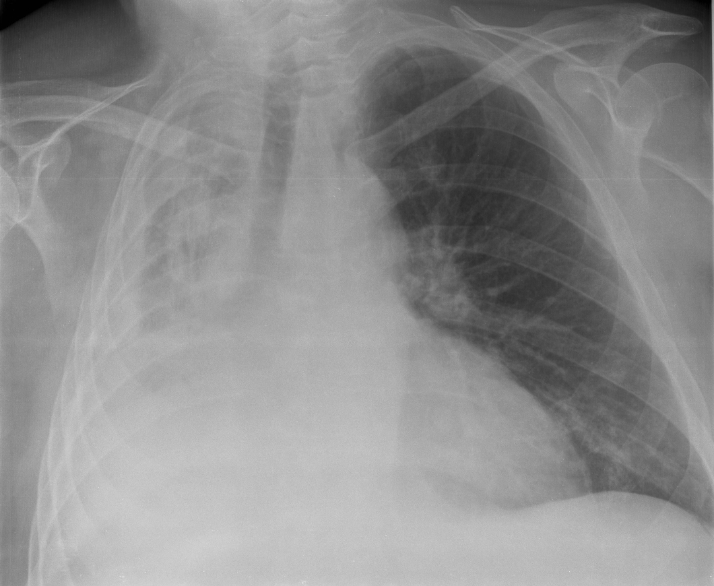

- Chest X-ray: This is the most common and effective way to confirm the diagnosis. The collapsed area will appear as a white, dense (opaque) patch.